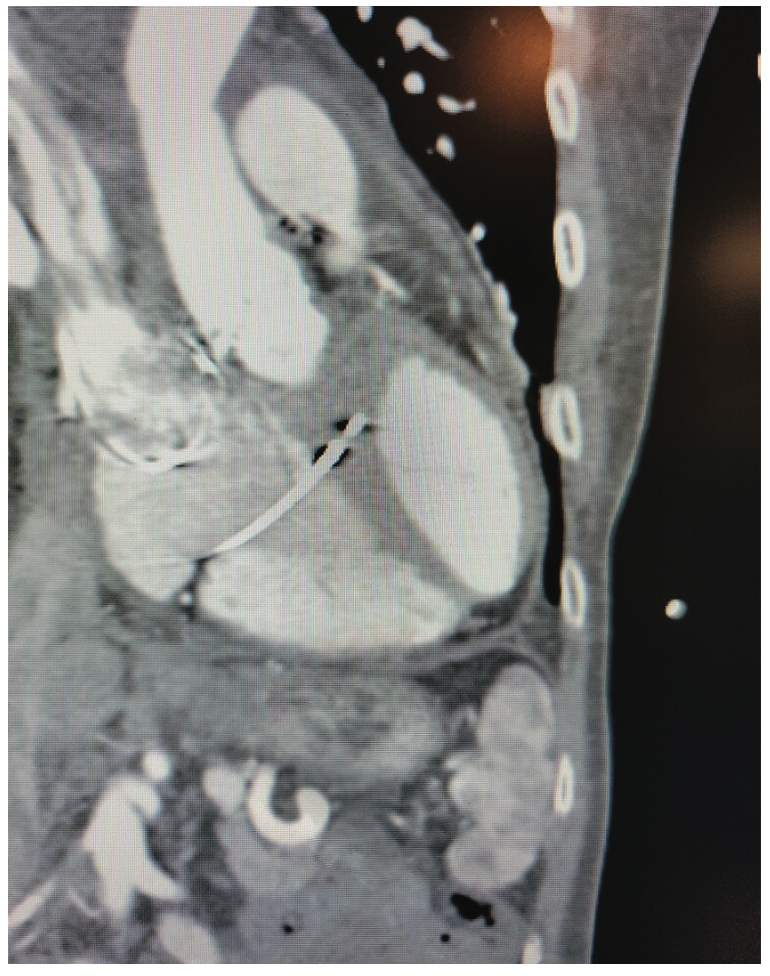

A 51-year-old male with history of prior coronary artery bypass grafting and bicuspid aortic valve replacement with severe aortic stenosis underwent elective percutaneous valve replacement with a 26 mm Sapien 3 Ultra transcatheter heart valve (Edwards). Left ventricular ejection fraction was normal. Baseline electrocardiogram (ECG) showed normal sinus rhythm and normal intervals (Figure 1). Postoperatively, he developed new symptomatic sinus node dysfunction, prolonged PR interval, LBB block (LBBB), and QRS duration of 160 milliseconds (Figure 2). After shared decision-making, the decision was made to implant a dual-chamber pacemaker with LBBAP. During the procedure, the atrial lead was initially placed in the RV for backup pacing. A C304-His sheath (Medtronic) was advanced over the wire into the mid RV. A 3830 SelectSecure lead (Medtronic) was then advanced through the sheath. Using the aortic valve and atrioventricular (AV) junction as a landmark, the fixation spot was chosen in 30º right anterior oblique (RAO) fluoroscopic view, about 1.5 cm distal to the AV junction. The sheath was pulled back to this spot and counter clocked on the septum at a 2 o’clock angle. The lead was screwed in place while watching for advancement of the tip on fluoroscopy. Impedance and injury current were checked after 5 turns. The lead was turned further until an impedance drop of 50-100 ohms was recorded. Left ventricular activation time (LVAT) was consistently 69 milliseconds at all outputs. The atrial lead was then pulled back and placed in the right atrial appendage. At the end, programming at nominal AV delays (150 milliseconds sensed, 180 milliseconds paced) caused fusion between paced and conducted QRS (Figure 3A). Shortening AV delay to 100 milliseconds sensed and 130 milliseconds paced returned a completely paced QRS complex (Figures 3B and 3C).

4. Take an image of the heart in 30º RAO view. The ideal implant region is along an imaginary line one-third of the way from the aortic valve to the apex of the RV (Figure 4), usually about 1.5 cm distal to the plane of the tricuspid annulus. The coronary sinus (CS) fat pad, valvular calcification, or valvular prostheses can help identify the location of the aortic valve and tricuspid valve annulus.